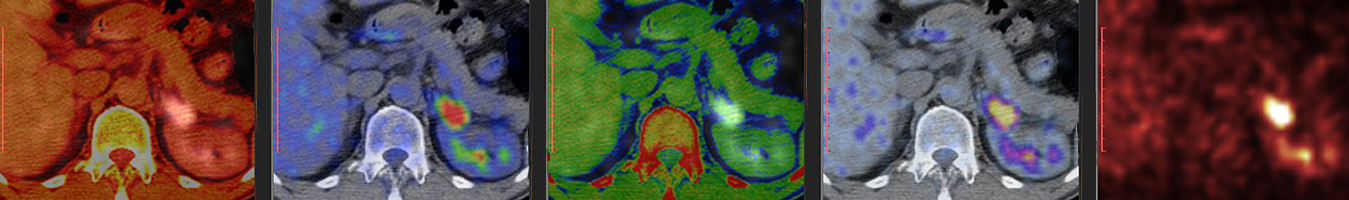

The Bioimaging and Applied Research Core, directed by Frank Corwin, Ph.D. and managed by Mackenzie Newman, Ph.D., offers comprehensive instrumentation and technical support for all aspects of in vitro and in vivo pre-clinical non-human anatomical and molecular imaging. Studies may be conducted on samples prepared to exhibit characteristic features for a particular imaging modality. Within the intact environment, physiological and pathophysiological activity may be observed through imaging or numerous biological pathways and interactions involved in injury and disease progression, such as traumatic brain injury, cardiac disease, tumorigenesis, and therapeutic interventions.

The BARC offers radionuclide imaging services of small animals on PET as well as non-radionuclide-based imaging using MRI/MRS, photoacoustic, and multispectral fluorescence systems. The facility also provides project consultation, user training, and staff-assisted data analysis services.

- LFER PET/CT in-vivo animal imager (Mediso USA), capable of large field-of-view (15 cm axial, 20 cm trans-axial), whole body preclinical imaging